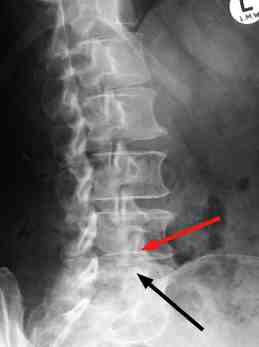

Injuries or overuse of the. It may be related to wear and tear arthritis can occur anywhere along the spine but is more frequent in the lower back and neck. Common lower back pain triggers.

It most commonly occurs when a herniated disk, bone spur on the spine, or narrowing of the spine (spinal stenosis) compresses part of the nerve.

The most common reason for lower right back pain is due to muscular, nerve, or other conditions related to the spine and pelvic bone. Other common sources of back pain muscle spasms, muscle fracture, abnormal curving of the spine (scoliosis), an inflamed sciatic nerve (the largest nerve in the body that runs from the lower part of the spinal cord through the. Lower back pain can become more intense when osteoarthritis affects the hips or the knees. A small fracture, in rare cases.